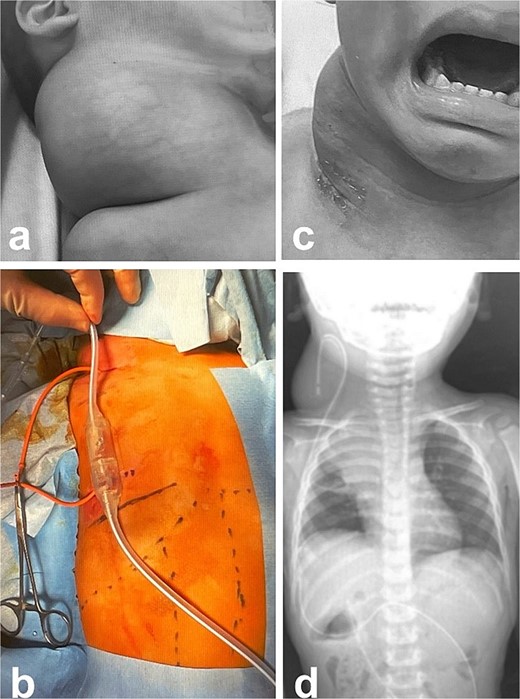

A male infant weighing 2726 g was born at 38 weeks of gestation. Antepartum ultrasonography and magnetic resonance imaging (MRI) revealed a right cervical cyst, suggestive of a lymphangioma. A right cervical cyst was noted at birth and gradually decreased in size thereafter. However, right cervical swelling became evident when he cried (Fig. 1a and b). An MRI obtained at 21 months of age showed a huge cyst in the right cervical mediastinal region. Following diagnosis of a lymphangioma with hemorrhage, he was treated with Eppikajutsuto®, a Japanese traditional Kampo medication, 2 g/d (0.2 g/kg). An MRI revealed tumor enlargement after oral administration of Eppikajutsuto® for 2 months. A complex vascular malformation was noted (Fig. 2) and the dose was increased to 5 g/day (0.5 g/kg). A repeat MRI 2 months after the dose increase showed no reduction in the size of the tumor. After another 4 months, the dose of Eppikajutsuto® was further increased to 7.5 g/d (0.65 g/kg). The tumor in the cervical region had enlarged further with an accompanying risk of airway system compression (Fig. 3a–c). A puncture and suction of the lymphangioma was performed for volume reduction and the content was prepared for bacterial culture. The content was dark red in color, which was consistent with hemorrhage. The white blood cell count (WBC) was 19 190/μl and the C-reactive protein (CRP) concentration was 5.77 mg/dl. He was admitted to the hospital to undergo treatment with intravenous and oral antibiotics. The bacterial culture results were negative. On the 22nd day of hospitalization, the WBC count was 8780/μl and the CRP concentration was 0.39 mg/dl. On the 24th day of hospitalization, a Denver shunt was inserted from the right cervical region to the abdominal cavity to reduce the volume of the cervical cyst to prevent airway obstruction (Fig. 4a–c). A pump chamber with a backflow prevention valve was implanted in the right anterior chest subcutaneous tissue (Fig. 4b). By applying pressure to the chamber, the cyst fluid in the neck was returned to the abdominal cavity. The patient was discharged on the 6th post-operative day. The swelling in the right neck was reduced and the pressure on the trachea was relieved based on the X-ray findings (Fig. 4c and d). On the 5th day after hospital discharge, the patient was febrile and the right neck swelling recurred. A hemogram revealed severe anemia and bleeding within the neck cyst was suspected. He was readmitted to the hospital and on the 2nd day after admission the cervical cyst was punctured, which yielded bloody contents. A transfusion was performed for anemia secondary to hemorrhage in the neck cyst. Sirolimus (1 mg), a mammalian target of rapamycin inhibitor, was added 7 months after starting Eppikajutsuto® due to a concern that administration of a Kampo medication and insertion of the Denver shunt might not be effective. An X-ray showed that the tip of the catheter may have moved within the cyst, which caused the catheter tip to penetrate the cyst and resulted in bleeding within the neck cyst (Fig. 5a). Serial MRI findings showed that the old bleeding site was within the mediastinal region of the lymphangioma. Revision surgery was performed 3 weeks after inserting the Denver shunt. Intraoperative findings showed that the tip of the catheter had penetrated the cyst wall (Fig. 5c). There were cyst walls with a septum on the mediastinal side of the cyst and when incised old bleeding was noted and the walls were opened as much as possible (Fig. 5d). The tip of the catheter was rounded and fixed with threads. The catheter was returned to the cyst and the wound was closed (Fig. 5b). The patient was discharged 9 days after the 2nd surgery. The concentration of sirolimus on the 14th day of administration was 9.9 ng/mL (normal range: 5–15 ng/ml). On the 16th day after the second hospital discharge, the neck had enlarged, the surgical wound was erythematous, and discharge was noted at the site of the pump chamber. Bacterial cultures of the punctured the neck cyst content and the wound discharge grew Staphylococcus aureus. On the 24th day after the 2nd hospital discharge, the blood concentration of sirolimus 1 month after starting oral administration was 19.7 ng/ml. Therefore, the oral administration of sirolimus was temporarily discontinued. At the same time the patient developed a high fever and the 3rd operation was performed to remove the Denver shunt due to a catheter infection. The blood concentration of sirolimus 6 days after discontinuation was 1.4 ng/ml. An MRI on the 6th post-operative day from the 3rd operation revealed two different intensities in the neck and mediastinal regions where the Denver shunt was inserted (Fig. 6a). On the 10th day after the 3rd operation, the patient was discharged from the hospital but laboratory testing showed an elevated WBC count (13 250/μl) and CRP concentration (6.03 mg/dl). Three months after the 3rd hospital discharge, the right neck swelling abruptly decreased in size and the WBC count and the CRP concentration decreased to the normal range. An MRI 2 months after the 3rd operation showed that the mediastinal lesion was smaller with near-complete regression (Fig. 6b). The neck swelling was minimal 6 months after the 3rd operation. An X-ray showed no tumor shadow and no compression of the trachea by the lymphangioma (Fig. 6c) and magnetic resonance angiography (MRA) showed that the lymphangioma had regressed (Fig. 6d). Currently, no right cervical swelling is evident when the patient cries (Fig. 6e and f) and he is doing well with oral administration of Eppikajutsuto® (7.5 g/d [0.65 g/kg]).

Intra- and post-operative findings from the first operation. (a) Intraoperative findings showed a huge bulge in the right neck. (b) A Denver shunt (peritoneovenous shunt) was inserted from the right cervical region to the abdominal cavity for volume reduction of the cervical cyst to prevent airway obstruction. Pump chamber with backflow prevention valve was implanted in the right anterior chest subcutaneous tissue. (c) Post-operative findings showed a reduction in the right neck swelling, even when crying. (d) The pressure on the trachea was shown to be relieved on the X-ray.